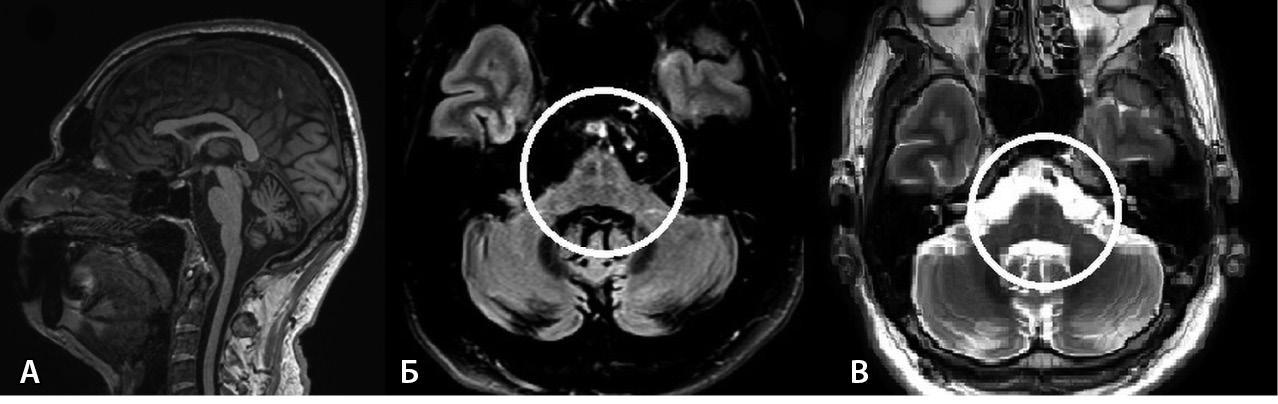

Проведены следующие дополнительные методы исследования. При УЗИ остаточной мочи ее объем составил 105 мл. На магнитно-резонансной томограмме (МРТ) головного мозга – признаки атрофии ствола мозга в режиме Т1, в режиме T2-FLAIR – симптом «креста» (рис. 1).

Рис. 1. Магнитно-резонансная томография головного мозга пациента В. А – Т1-взвешенное изображение, сагиттальный срез: признаки атрофии варолиева моста в виде уплощения его основания, а также расширение борозд мозжечка. Б, В – Т2-FLAIR, Т2-взвешенное изображение, аксиальные срезы: симптом «креста», или “hot cross bun”: гиперинтенсивность волокон мосто-мозжечковых путей и ядер шва (отмечено кругом)

На основании вышеуказанного, согласно критериям диагностики МСА от 2022 г., пациенту В. был выставлен клинический диагноз достоверной МСА-М.